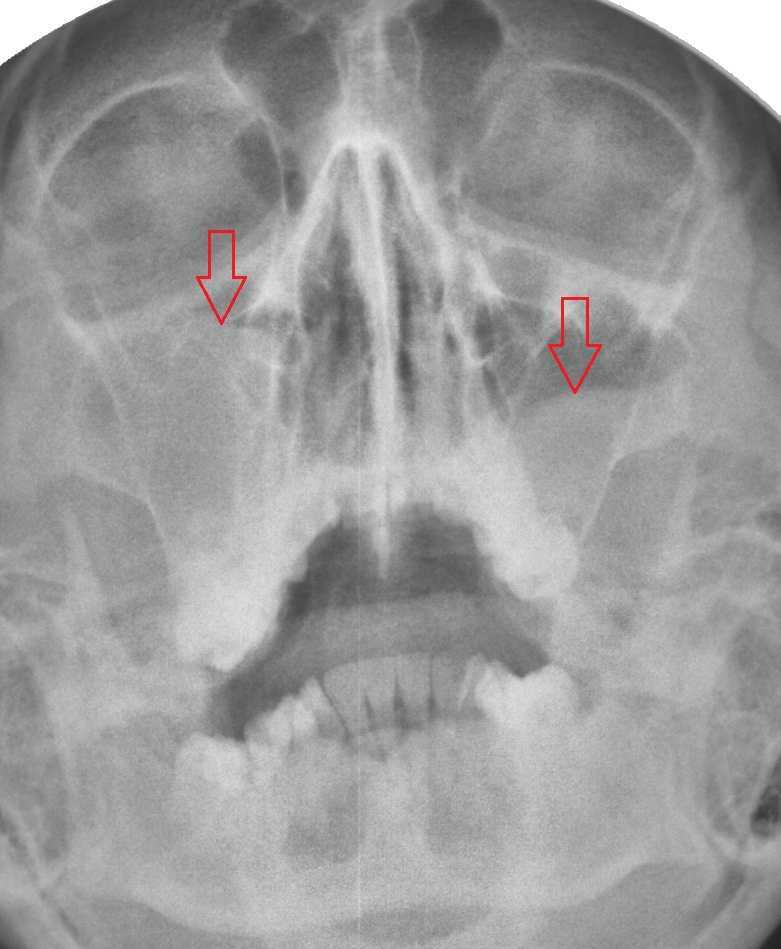

КТ-снимки хронического этмоидита: подробная визуализация